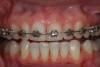

(13.) Retracted view of a patient who had been using tray application of 10% carbamide peroxide for over a year to clean the braces as well as bleach the teeth.

Figure 13

(14.) Smile photograph of the patient in Figure 13 immediately after removal of the arch wires and brackets, showing no white spot lesions or any yellow spots where the the bonded brackets were previously located.

Figure 14